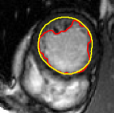

V-B Ventricle Segmentation: Comparison of Three Registration Schemes

In this experiment, we focus on real cardiac MRI data and compare registration methods used for segmentation of the LV and RV. We visually compare the tracking results given by our method to (M1) registration of only the interior of current estimate of the ventricle to a subset of next image (to show whole image registration is needed), and to (M2) standard full image registration with global smoothness. M1 is achieved by computing just the inside velocity with Neumann boundary conditions on (normal constraint does not apply in M1). The best results with respect to ground truth are chosen by choosing the optimal parameter in all methods. Results on LV and RV tracking for a full cardiac cycle are given in Figure 6 for the LV and Figure 7 for the RV. Registering only the organ (M1) results in errors (as the background registration is helpful in restricting undesirable registrations of the foreground). Globally smooth registration (M2) smooths motion from irrelevant background structures into the ventricles, which results in drifting from the desired boundary. Our method, which smooths within regions with satisfying the physical constraint, is able to achieve the most accurate results.